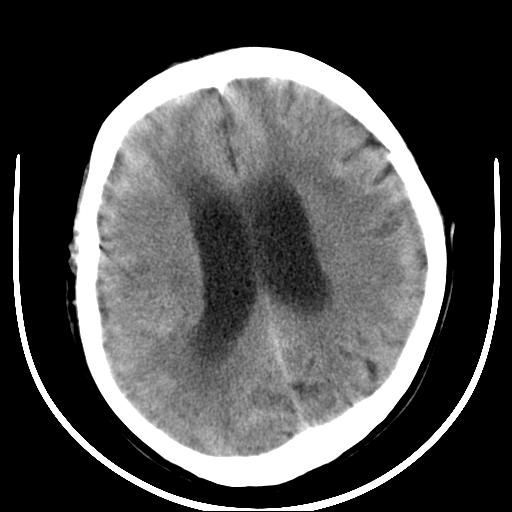

标题: CT16838:男58岁,意识不清2小时,请会诊出血部位该如何写。 [打印本页]

标题: CT16838:男58岁,意识不清2小时,请会诊出血部位该如何写。

图像质量太差,真不好确定,左基底结出血应该没有问题,再有就是蛛网膜下腔和脑干是否有出血,请老兄建议你们领导换机器吧

1)脑干、左侧桥小脑臂及小脑蚓部出血破入蛛网膜下腔。2)左侧基底节区灶性出血,不排除钙化灶。3)脑室系统少量积血。4)脑积水。

(患者病情危重,出现不自主运动——是引起图像质量不佳的主要原因)